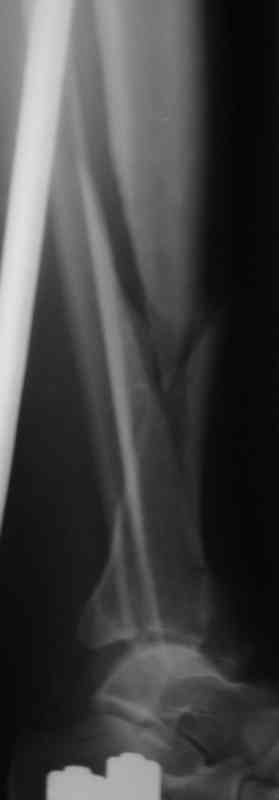

Судя по снимкам (спиральный перелом диафиза продолжающийся до сустава, отрывной перелом внутренней лодыжки) механизм перелома - скручивание. Стоит сделать снимок на всю голень включая коленный сустав и поискать проксимальный перелом м.берцовой кости. Такие переломы сопровождаются разрывом межкостной мембраны и поэтому нестабильны, повреждение м.т.

значительное и как правило большие гематомы.

Внутрисуставной перелом простой - линейный, по этому не должно быть проблем с закрытой репозицией на ЭОПе. По моему мнению самый подходящий метод -